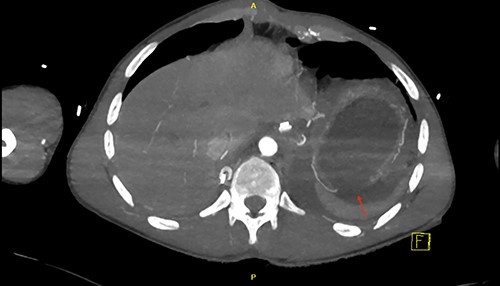

CT scan revealed a large left haemothorax and evidence of left diaphragmatic rupture with herniation of abdominal organs to thoracic cavity such as the spleen, stomach and splenic flexure of the colon; fractured all 12 left ribs, pulmonary contusion, unstable fractures of T6, T10 with acute spinal cord injury (complete transection; Figs 1–3).

Sagittal view of CT scan demonstrates a level of the left hemidiaphragm.